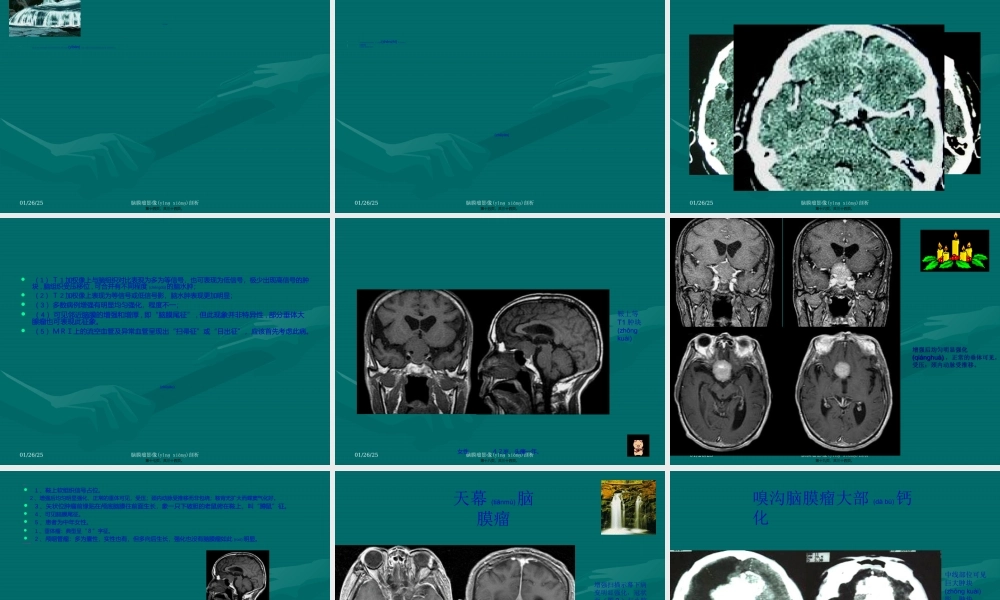

脑膜瘤脑膜瘤CTCT、、MRIMRI表表现现(biǎoxiàn)(biǎoxiàn)第一页,共三十四页。01/26/25脑膜瘤影像(yǐnɡxiànɡ)剖析(pínɡshù)•脑膜瘤起源于蛛网膜细胞丛,与蛛网膜颗粒关系密切,是典型的脑外肿瘤。多见于中年人,女性多于男性,好发于矢状窦旁,大脑凸面,蝶骨嵴,嗅沟,桥小脑(xiǎonǎo)角,大脑镰或天幕。少数发生于脑室内,多为单发。脑膜瘤常见的病理类型包括:⑴内皮型:肿瘤有蛛网膜上皮细胞组成,是最常见的类型。⑵纤维型:由纤维母细胞和胶原纤维组成。⑶血管瘤型:瘤内有丰富的血管成分。⑷砂粒型:瘤内含有大量砂粒体。⑸混合型:也较多见,瘤内含有上述四种成分。⑹恶性脑膜瘤:细胞形态及生长特征具有恶性肿瘤的特点,且可以发生转移。第二页,共三十四页。01/26/25脑膜瘤影像剖析(biǎoxiàn)•(一)常表现为边界清楚的肿块,以宽基底与颅骨内板或硬脑膜相贴。(如病变中心(zhōngxīn)发生于额顶上部,由于CT横断面扫描的局限性,部分病变似脑内占位,CT冠状面、矢状面重建及MRI有助于显示病变特征。)平扫右侧额叶见等密度肿块,外侧(wàicè)与颅板相贴,周围见大片水肿,占位效应明显。增强后明显均匀强化,CT值上升约110Hu。第三页,共三十四页。01/26/25脑膜瘤影像(yǐnɡxiànɡ)剖析•(二)平扫常为均一略高或高密度肿块,钙化常见,常为细小点状、沙粒状或不规则,罕见整个瘤体钙化(见下图)。增强扫描呈均一明显强化。边界清楚锐利。少数病例还可显示肿瘤(zhǒngliú)周边有一薄层环状强化影(见下图),可能是肿瘤(zhǒngliú)包膜所含血管较丰富和包绕肿瘤(zhǒngliú)的静脉或引流静脉较多所致。CTCT表现表现(biǎoxiàn)(biǎoxiàn)第四页,共三十四页。01/26/25脑膜瘤影像剖析(shǎojiàn)•女性(nǚxìng),55岁,头昏、头痛2年,加重一月。CTCT表现表现(biǎoxiàn)(biǎoxiàn)第五页,共三十四页。01/26/25脑膜瘤影像(yǐnɡxiànɡ)剖析诊断依据:1、病变呈类圆形,实性部分明显强化,内侧低密度坏死区内见液液平面,密度下高上低,考虑为瘤内出血所致;2、病灶外缘与脑膜(nǎomó)呈广基相贴,骨窗示相连的颅骨骨质较对侧更厚,且内板边缘明显,较毛躁而不光整锐利;3、占位性病变周围右侧额叶脑实质见低密度水肿带,脑室及中线结构移位。病理诊断:右侧额叶镰旁“囊性脑膜瘤伴瘤内出血”鉴别诊断:主要和胶质瘤进行鉴别,胶质瘤的总体强化程度不如脑膜瘤,其病灶密度较低且常不均匀。第六页,...